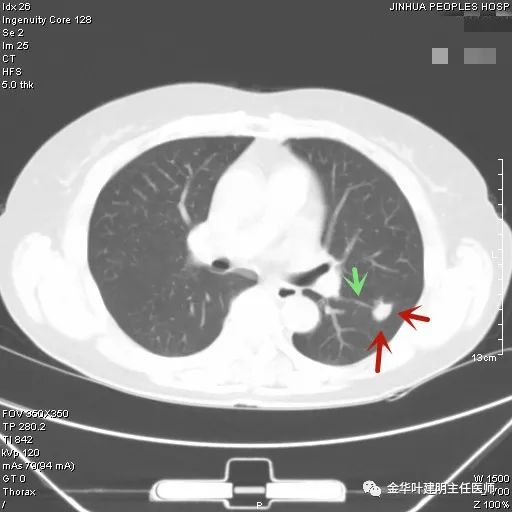

上图示结核。我们发现其有明显的卫星灶,如绿色箭头所示,主病灶处也是周边有模糊区域,病灶整体密度较为均匀(肿瘤容易生长不均致密度欠均匀,显杂乱)。

叶建明谈实性结节,叶建明肺实性良性结节会变癌症吗